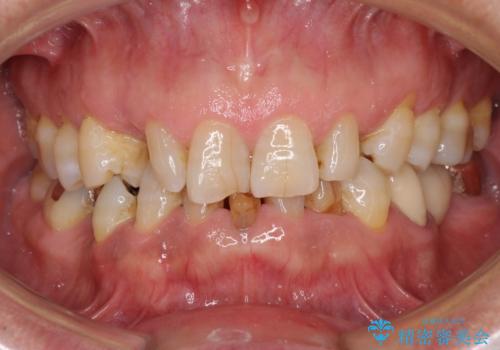

- 乳歯や矮小歯が多くある前歯部の審美障害が気にして来院された患者様です。

上顎の矮小歯は隙間が多く、歯軸の傾斜も大きかったため、部分矯正により補綴治療前に歯の位置を整えることとしました。

下顎の乳歯は支台歯として機能することは困難と思われたので、事前に抜歯をし、上顎の矯正治療終了のタイミングに合わせて、セラミックブリッジにて補綴治療することとしました。